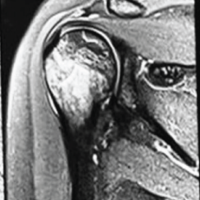

The patient is a 44-year-old female who presented with a progressively enlarging, painful swelling in the left distal femur. The swelling had been present for several months and was associated with localized pain that worsened over time. Radiographic imaging (Fig. 1) revealed an osteolytic lesion in the distal femur with ill-defined margins and a narrow zone of transition, suggestive of a GCT (Campanacci grade 2). Magnetic resonance imaging (MRI) of the lesion (Fig. 2) was done which revealed a well-defined lesion in epi-metaphyseal lesion measuring 64 × 52 × 38 mm on the left side of distal femur, associated with a large soft tissue mass, with no intra-articular extension.

Figure 2: Magnetic resonance images. (a) T2w coronal image, (b) T1w coronal image, (c) T2w axial image, (d) T2w sagittal image showing lesion in the distal aspect of left femur.